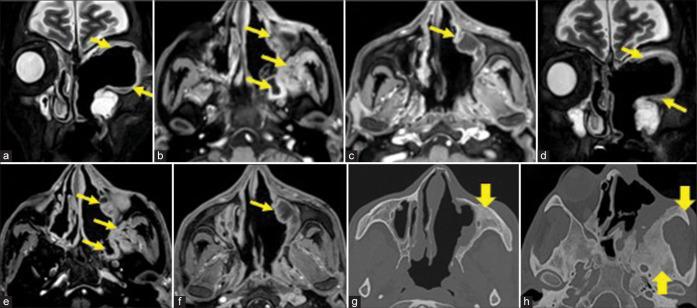

The most frequent MRI finding was T2 hypointensity in the sinonasal mucosa (94%) followed by mucosal necrosis/loss of contrast-enhancement (92.6%). Extrasinosal inflammation with or without necrosis in the pre-antral fat, retroantral fat, pterygopalatine fossa, and masticator space was seen in 91.1% of the cases. Extrasinosal spread was identified on MRI even when the computed tomography (CT) showed intact bone with normal extrasinosal density. Orbital involvement (72%) was in the form of contiguous spread from either the ethmoid or maxillary sinuses; the most frequent presentation being orbital cellulitis and necrosis, with some cases showing extension to the orbital apex (41%) and inflammation of the optic nerve (32%). A total of 22 patients showed involvement of the cavernous sinuses out of which 10 had sinus thrombosis and five patients had cavernous internal carotid artery involvement. Intracranial extension was seen both in the form of contiguous spread to the pachymeninges over the frontal and temporal lobes (25%) and intra-axial involvement in the form of cerebritis, abscesses, and infarcts (8.8%). Areas of blooming on SWI were noted within the areas of cerebritis and infarcts. Perineural spread of inflammation was seen along the mandibular nerves across foramen ovale in five patients and from the cisternal segment of trigeminal nerve to the root exit zone in pons in three patients. During follow-up, patients with disease progression showed involvement of the bones of skull base, osteomyelitis of the palate, alveolar process of maxilla, and zygoma. Persistent hyperenhancement in the post-operative bed after surgical debridement and resection was noted even in patients with stable disease.

Contrast-enhanced MRI must be performed in all patients with suspected AIFRS as non-contrast MRI fails to demonstrate tissue necrosis and CT fails to demonstrate extrasinosal disease across intact bony walls. Orbital apex, pterygopalatine fossa, and the cavernous sinuses form important pathways for disease spread to the skull base and intracranial compartment. While cerebritis, intracranial abscesses, and infarcts can be seen early in the disease due to the angioinvasive nature, perineural spread and skull base infiltration are seen 3-4 weeks after disease onset. Exaggerated soft-tissue enhancement in the post-operative bed after debridement can be a normal finding and must not be interpreted as disease progression.